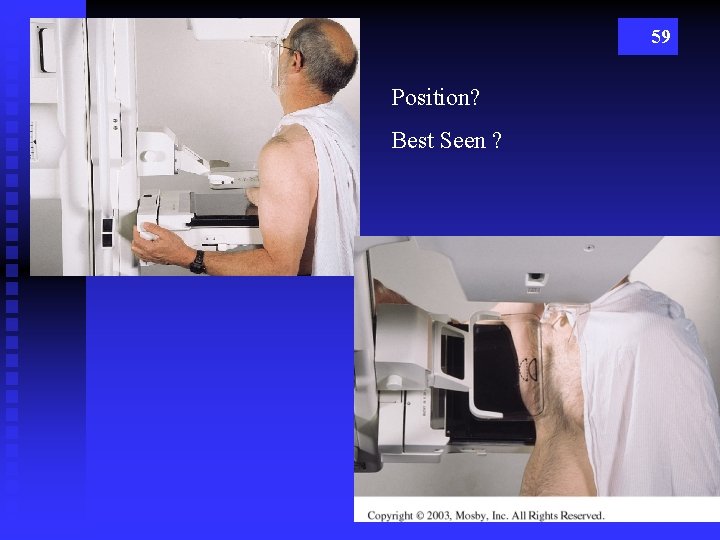

59 Position? Best Seen ?

60 male breast